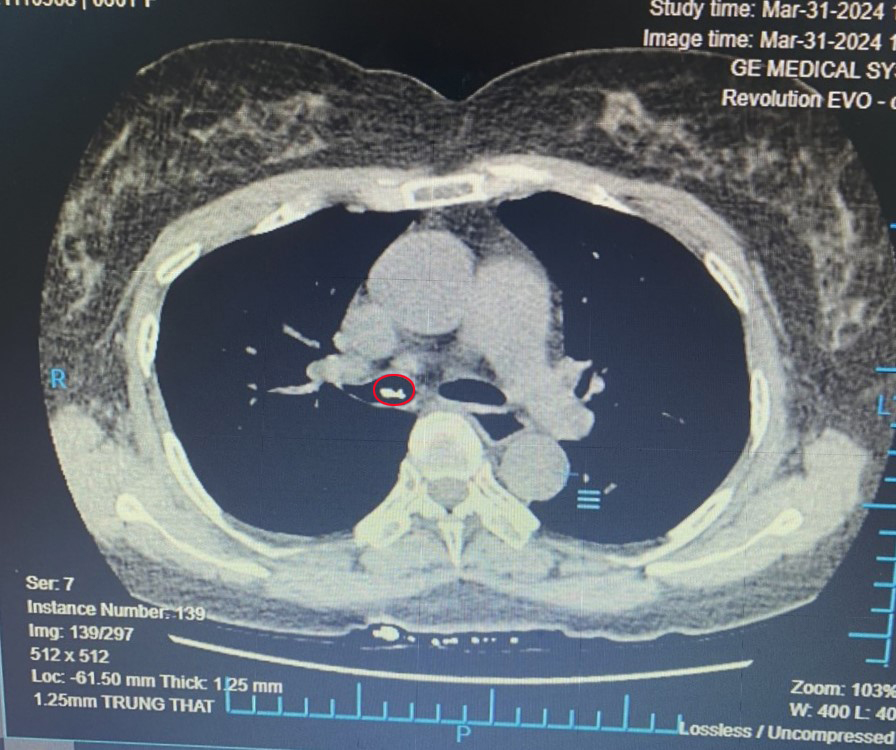

- Hình ảnh dị vật phế quản gốc phải qua CT Scanner

Trước khi vào viện 1h, bệnh nhân nữ 61 tuổi đang ăn cá đột ngột thấy nuốt đau, ho, đau ngực phải. Bệnh nhân đã khám tại cơ sở y tế khác soi không phát hiện thấy xương. Tiếp nhận người bệnh tại Bệnh viện đa khoa quốc tế Hải Phòng, các bác sĩ đã thăm khám, hỏi bệnh tỉ mỉ và với kinh nghiệm dầy dặn, bác sĩ đã nghĩ đến khả năng bệnh nhân bị sặc dị vật vào đường thở mà không phải mắc tại thực quản như các trường hợp thông thường. Do đó, bác sĩ thăm khám đã chỉ định cho bệnh nhân chụp CT scanner ngực và kết quả hình ảnh chụp CT ngực phát hiện dị vật trong phế quản gốc phải. Nhanh chóng, các bác sĩ quyết định thực hiện nội soi phế quản dưới gây mê và gắp thành công dị vật là mảnh xương cá, kích thước 4x3cm cho bệnh nhân.